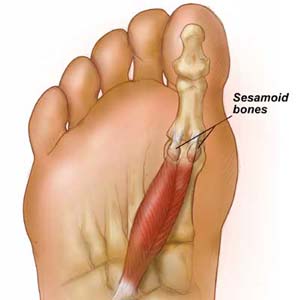

Sesamoiditis Big Toe Joint Pain Ohio Foot Ankle Specialists

Sesamoiditis Symptoms Treatment My FootDr

Sesamoiditis